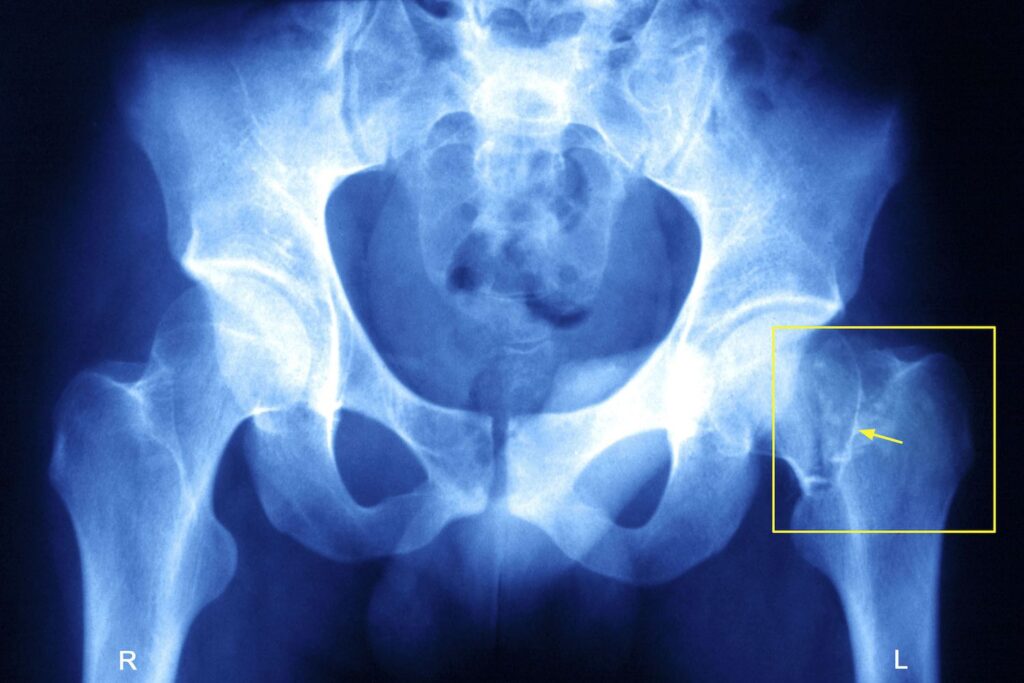

Diagnosis Of Hip Fracture

At Melbourne Orthopaedic Clinic, diagnosing a hip fracture begins with a physical examination to assess range of motion, strength, and discomfort. Diagnostic imaging confirms the diagnosis and determines fracture type and location:

- X-rays: The primary imaging method for hip fractures, X-rays reveal the location and severity of the break.

- MRI or CT Scan: For complex fractures or when X-rays are inconclusive, MRI or CT scans provide detailed images of soft tissue and bone structure, ensuring accurate diagnosis.